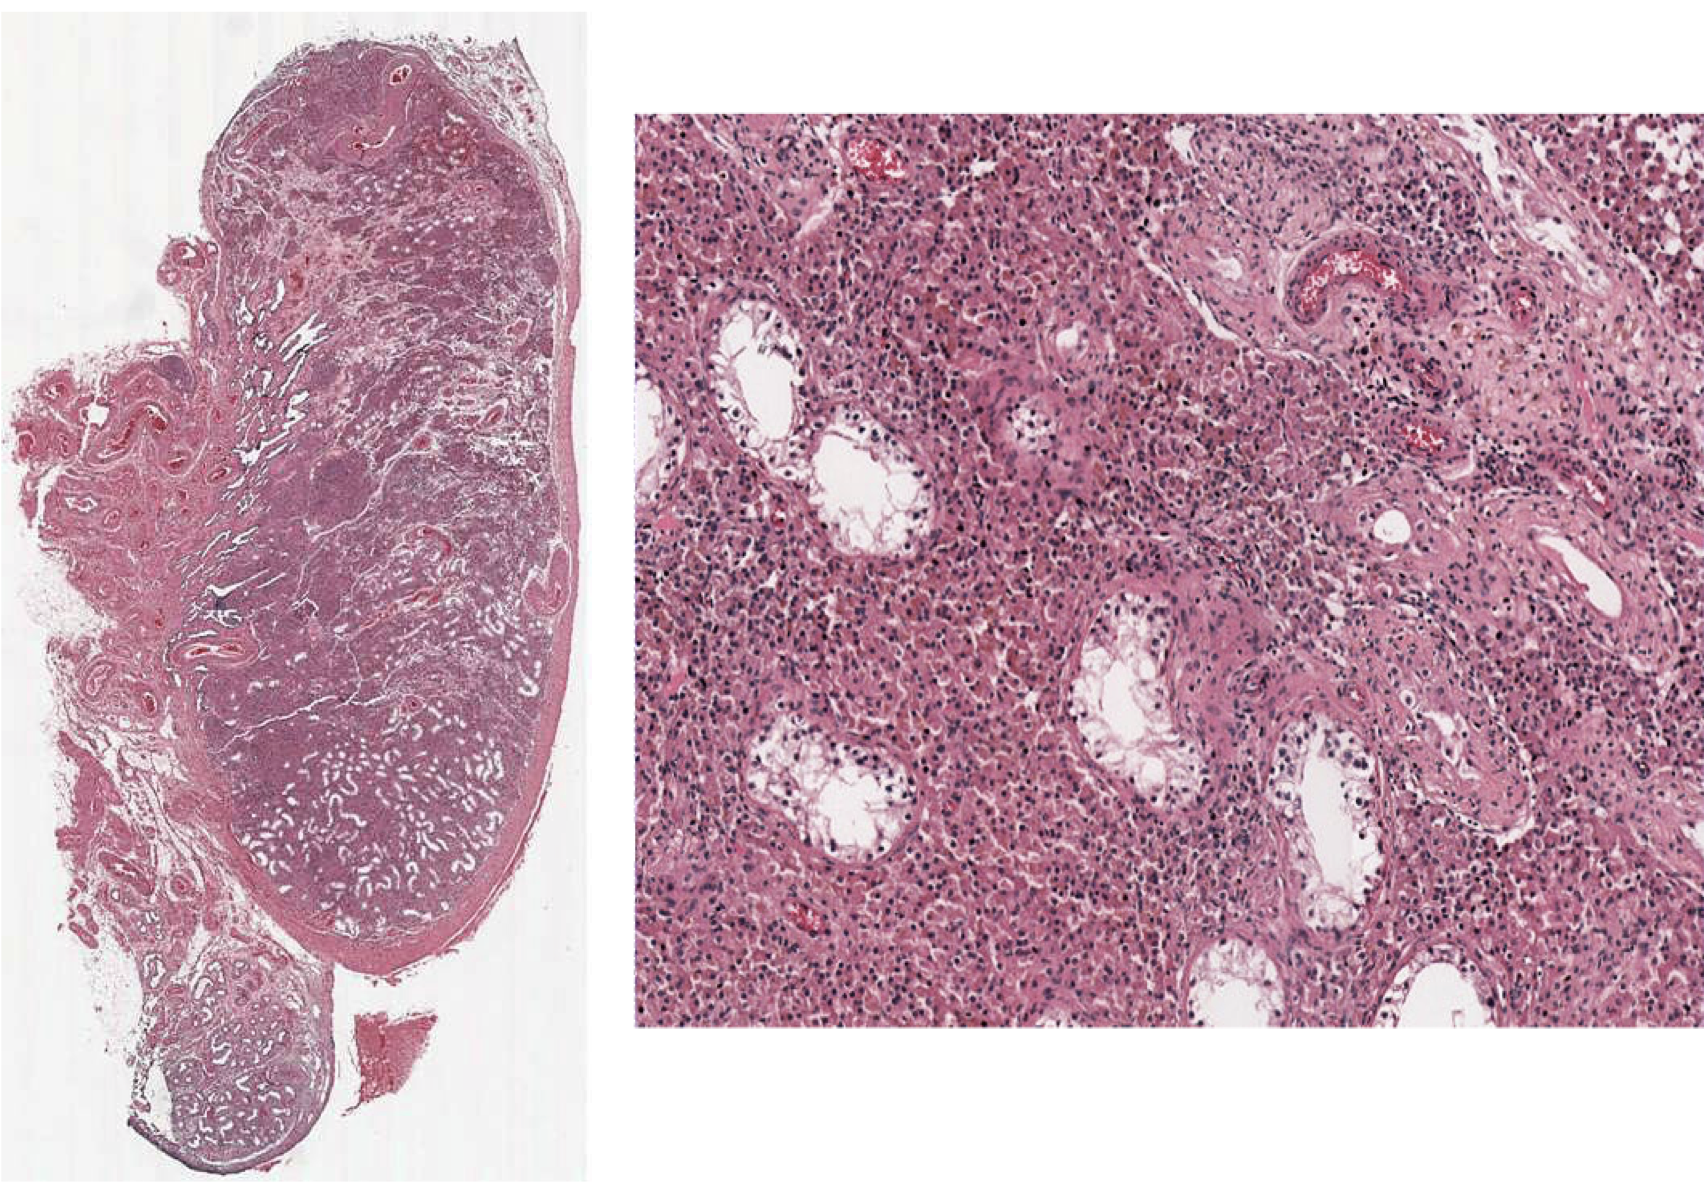

Testicular Lymphoma

Lymphoma